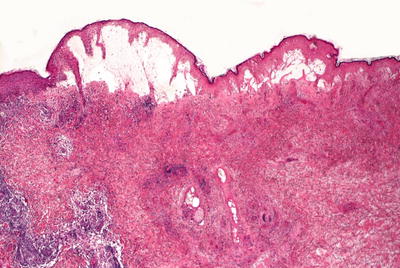

Fig. 14.5

Scabies are present within the stratum corneum in a case of Norwegian scabies. They are abundant and readily apparent on H&E stains

Fig. 14.6

Female mites are present within the stratum corneum in Norwegian scabies